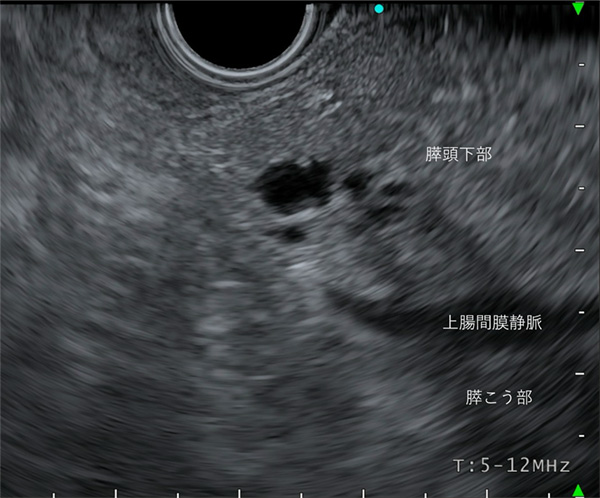

〈十二指腸下行脚操作による観察〉

胆管と膵管の合流部であるVater乳頭を描出します。ここでは、膵頭部および、膵頭下部、膵こう部を観察することが可能です。

膵頭下部、膵こう部も一般的に腹部エコーでの病変描出は困難な部位です。本症例は、腹部エコーで指摘されなかった、膵頭下部に、膵IPMN(10mm)をこの超音波内視鏡でみつけた一例です。膵癌のリスクファクターとされる病変です。EUSの有用性がしめされた一例となります。